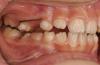

LeFor Опубликовано 22 сентября, 2013 Поделиться Опубликовано 22 сентября, 2013 еще есть вот такой, жесткий вариант... 2 Ссылка на комментарий

CRAZYDUCK Опубликовано 27 января, 2014 Поделиться Опубликовано 27 января, 2014 еще есть вот такой, жесткий вариант...с какой целью эта конструкция ? Судя по зубам - рынку уже лет девять ( ну восемь) , место для 5.4 лет до 8 надо держать , в чем причина фиксации этой конструкции ? Если она давно была зафиксирована , то поделитесь опытом . Как они стоят , много Вы их уже фиксировали ? Не отклеивает их дети? Ссылка на комментарий

LeFor Опубликовано 3 февраля, 2014 Поделиться Опубликовано 3 февраля, 2014 Эта конструкция- результат нежелания родителей платить за профилактику, иногда попадается такая категория... это стальная 19х25, стоит годами... аж заржавела)) по мнению Тихонова и Попова склонность к мезиализации есть чуть ли не всю жизнь. и кто может утверждать что этот зуб прорежется точно в срок? Ссылка на комментарий